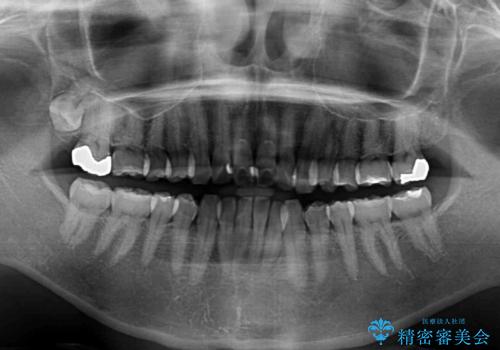

- 少しだけ前に飛び出ている前歯を気にして来院された患者様です。

上顎歯列全体を後方に移動させる必要があり、インビザライン単体での治療は困難と判断し、補助装置により左右側方歯列を移動させた後にインビザラインを用いることとしました。

インビザライン単独でも上顎歯列全体を後方移動することで臼歯の咬み合わせを改善できる場合もあります。しかしながら、矯正治療は当初設定したゴールに到達する必要があり、今回のような場合ではインビザライン単独では達成の可能性が低くなるので、補助装置を使用して、より確実に治療を行うこととしています。